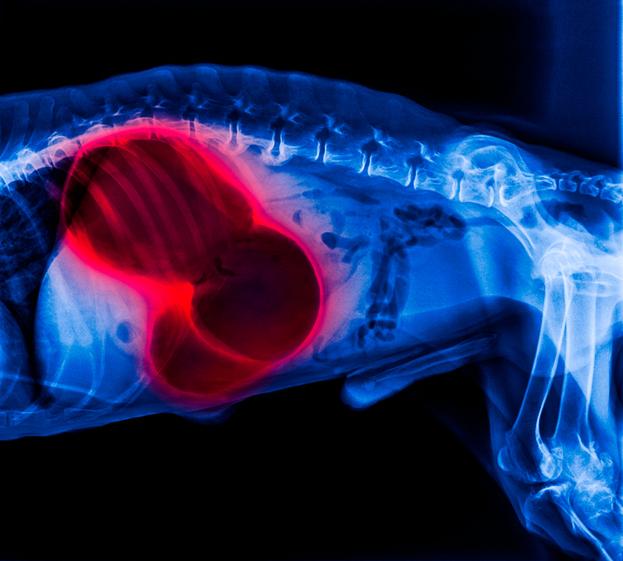

La distensión abdominal es un proceso mediante el cual el abdomen aumenta de tamaño y cambia su forma, volviéndose más redondeado y prominente. Este incremento de la cavidad abdominal puede ser por el acúmulo de líquidos, gases u órganos que aumentan de tamaño de forma anormal. Como se observa, los perros con distensión abdominal pueden estar sufriendo una gran variedad de enfermedades que pueden afectar a su salud, por lo que es importante acudir a un veterinario lo antes posible para detectar la causa principal e intentar solucionar la patología.

- Diagnóstico por imagen: la radiografía y la ecografía, tanto abdominal como torácica, también pueden ayudar a descartar patologías de otros órganos como el corazón, el hígado, el bazo o la vejiga, entre otros.